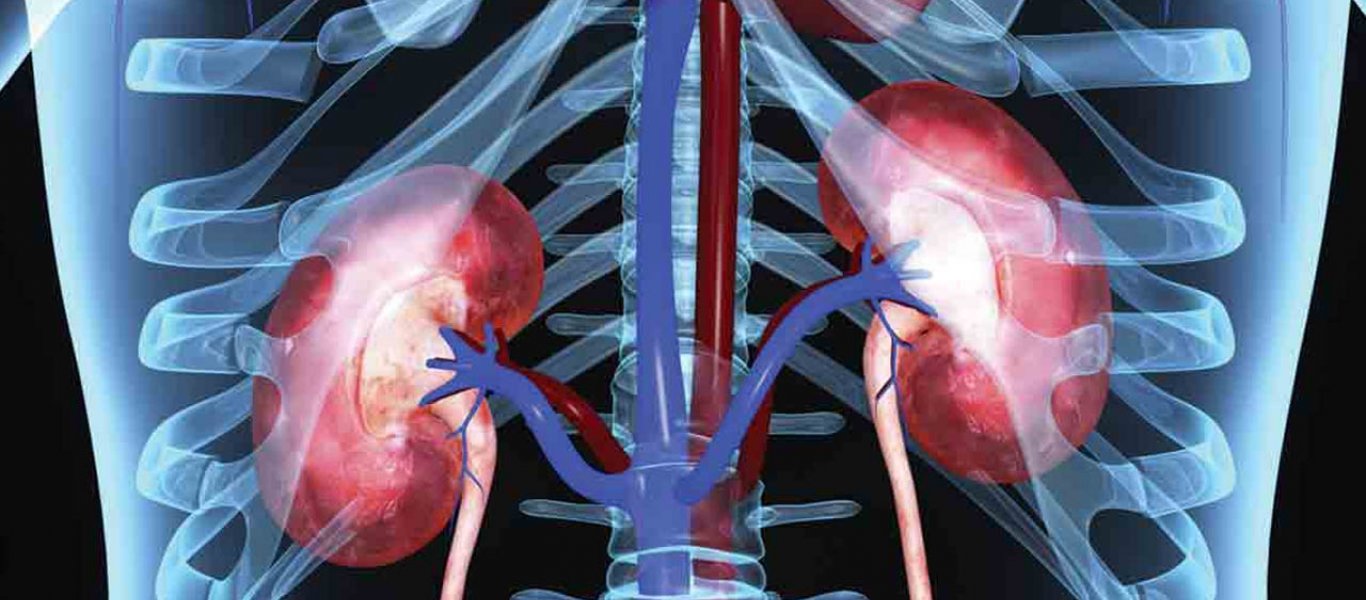

Οι βλαβερές διατροφικές συνήθειες συμβάλλουν στη δημιουργία στέρεων σχηματισμών στον ουρικό σωλήνα και τα νεφρά.

Υπολογίζεται ότι το 80% της πέτρας των νεφρών αποτελείται από κοιτάσματα ασβεστίου.

Γι’ αυτό και πρέπει να αποφεύγετε τροφές με υψηλή περιεκτικότητα με υψηλό οξαλικό οξύ.

Τέτοιες είναι:

Το σπανάκι, η μελιτζάνα, η ντομάτα, η πατάτα, τα φιστίκια, η ζάχαρη, τα αμύγδαλα και το κακάο. Τον κίνδυνο δημιουργίας πέτρας στα νεφρά μπορεί επίσης να αυξήσει η πρόσληψη υψηλής ποσότητας ζωικού λίπους.

Σύμφωνα με τα αποτελέσματα ερευνών, το γκρέιπφρουτ επίσης μπορεί να ενισχύσει τον κίνδυνο ανάπτυξης πέτρας στα νεφρά. Καλό είναι επίσης να αποφεύγετε όλα τα είδη των τροφίμων που μπορούν να αποσπάσουν νερό από το σώμα προκαλώντας αφυδάτωση.

Αυτά περιλαμβάνουν το αλκοόλ, τον καφέ, τη ζάχαρη, το πολύ ασβέστιο κ.λπ.

Επιβάλλεται τέλος να πίνετε πολύ νερό, που συνεπάγεται συχνότερη ούρηση και συντελεί στην αποβολή των ιχνοστοιχείων που προκαλούν τον σχηματισμό λίθων στους νεφρούς, μειώνοντας έτσι το ενδεχόμενο να μένουν στάσιμα και να σχηματίζουν μάζες στο ουροποιητικό σύστημα